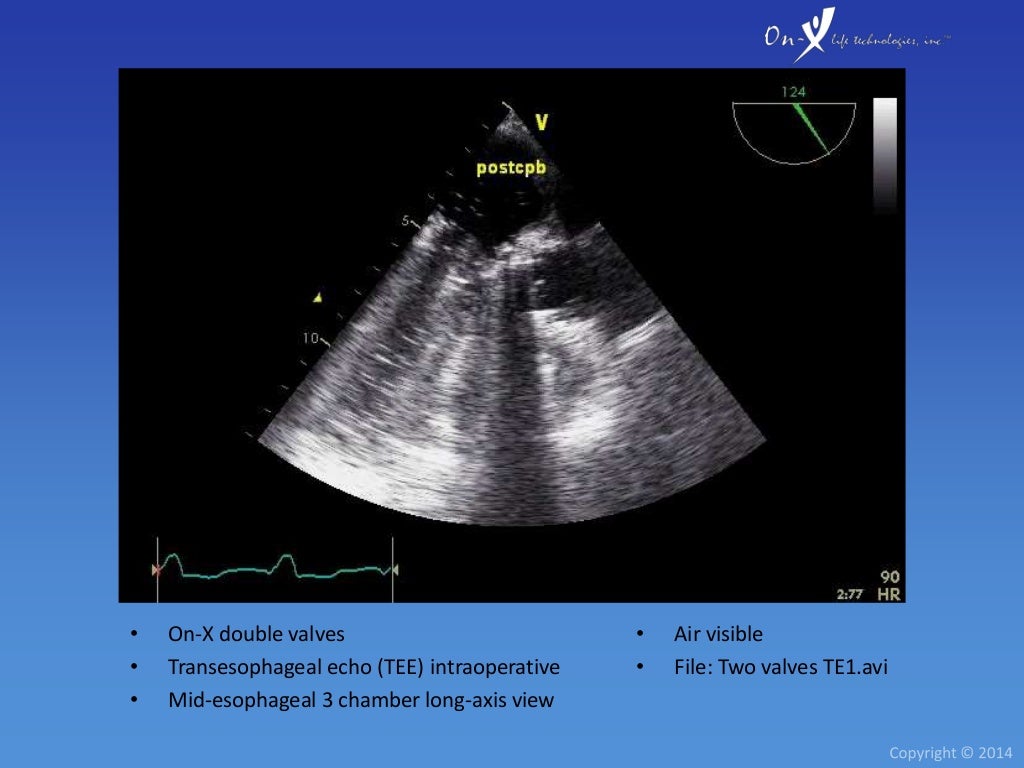

From www.broadcastmed.com

Minimally Invasive Mitral Valve Replacement Using OnX® Mitral Heart On-X Valve And Mri A patient with this device. Some have no metallic components and are mr safe at all field strengths. Facilitates mitral valve replacement in patients presenting with mitral annular calcification (mac) 10. Designed to serve as a buffer reducing paravalvular leaks. This letter summarizes the required mri information for all sorin group heart valve prostheses and annuloplasty devices. Bioprosthetic valves are. On-X Valve And Mri.